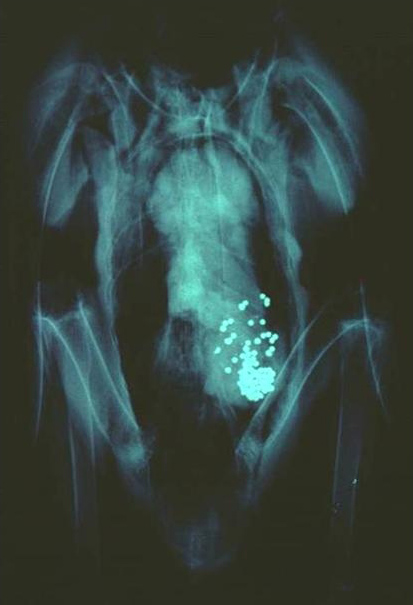

They are certainly not lost to the countless individuals of numerous species who eat the spent lead shot, the wayward bullets, the lost fishing sinkers, and the snagged the tackle. They are decidedly not lost to the wildlife that eats the dead and wounded animals who were shot, or who ate the lead.

“Science is replete with evidence that ingestion of spent ammunition and fishing tackle can kill birds,” said Barnett Rattner, one of the report’s authors. “The magnitude of poisoning in some species such as waterfowl, eagles, California condors, swans and loons, is daunting. For this reason, on July 1, 2008, the state of California put restrictions on the use of lead ammunition in parts of the range of the endangered California condor because the element poses such a threat to this endangered species.”

Lead poisoning causes behavioral, physiological, and biochemical effects, and often death. The rate of mortality is high enough to affect the populations of some wildlife species. Not to mention the hunters who eat them. Is this why hunting is on the decline?